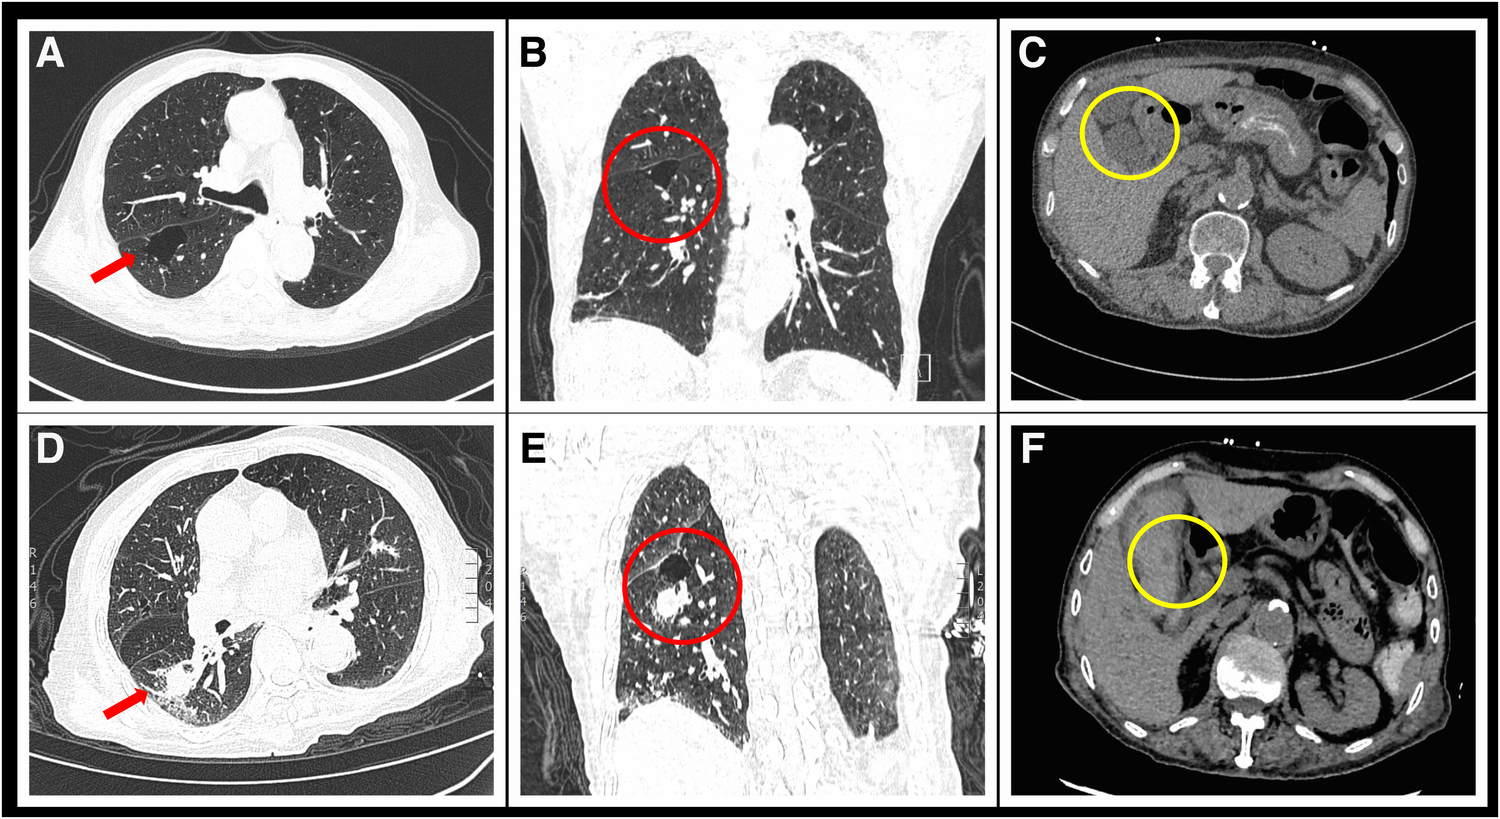

Figure 1

Comparison of chest and abdominal CT scans before and after admission. (A) Transverse section of chest HRCT upon admission shows a large bulla in the red arrow region due to COPD. (B) Coronal section image of the chest before hemoptysis shows a newly developed solid nodule in the right lung. (C) Abdominal CT at admission shows no abnormalities in the gallbladder artery. (D) Follow-up chest HRCT image 1 week after admission shows a new solid nodule with a diameter of 21 × 18 mm in the posterior segment of the right lower lobe (red arrow). (E) Coronal section image of the chest after hemoptysis shows a newly developed solid nodule in the right lung. (F) Emergency abdominal CT image taken after abdominal pain and vomiting shows a newly appeared circular low-density dark area at the gallbladder artery (yellow circle).

On the seventh day after admission, the patient experienced four sudden and unexpected episodes of hemoptysis, with each episode producing approximately 30–50 ml of blood. Hemostatic medication, i.e., etamsylate, hemocoagulase bothrops atrox and tranexamic acid, was administered immediately, and a repeat HRCT scan of the lungs revealed the presence of a newly formed solid nodule in the posterior segment of the right lower lobe (Figure 1D). Further contrast-enhanced CT imaging confirmed the diagnosis of a pseudoaneurysm of the pulmonary artery in the same location (Figure 2).

After the cessation of hemoptysis, the patient developed severe right upper abdominal pain and recurrently vomited fresh blood. Emergency abdominal CT scan revealed acute cholecystitis with biliary bleeding (Figure 1F). With the assistance of interventional doctors, percutaneous cholecystocentesis and drainage were performed, resulting in the extraction of approximately 150 ml of bloody fluid. To identify the cause of abdominal pain and vomiting, we conducted computed tomography angiography (CTA) of the entire aorta, which revealed a newly formed pseudoaneurysm in the gallbladder artery (Figure 3).